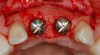

Figure 2  The orientation of the healing abutments after the patient had undergone extraction, guided bone regeneration, and implant placement. Note the wide spacing between the central incisor implants.

Figure 2